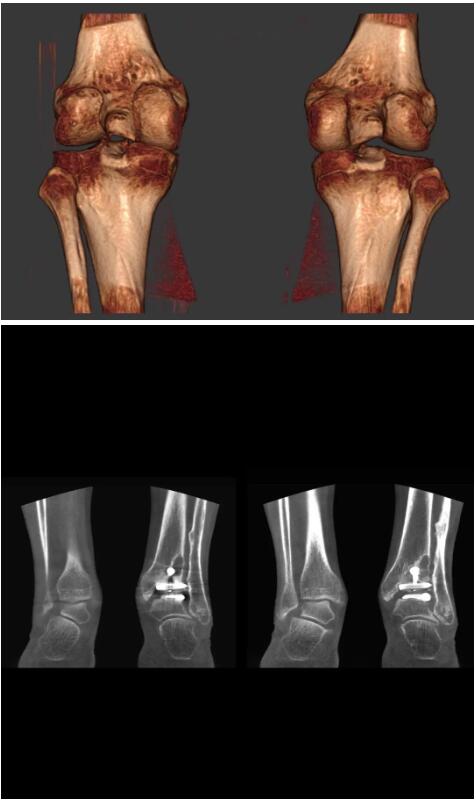

另外一款被稱為世界上最小的CT,它的重量僅300磅,不僅能夠掃查足部,還可以檢查膝蓋和上肢等。

與上面介紹的CT一樣,它同樣具有輻射低、占地空間小(23*36)的特點,隨開隨用(支持直接接入墻上的插座)。

這款CT使用非常方便,通過上下移動保持與患者的手臂或者雙腿齊平,掃描快速,僅需要30秒左右就可以完成掃查。

以上介紹的CT均來自國外同一家公司,這些CT均配置了可視化軟件,可以進行切片、3D重建以及大型CT附帶的所有典型的操作功能。

以下是這些“特立獨行”的CT所拍出來的圖像: